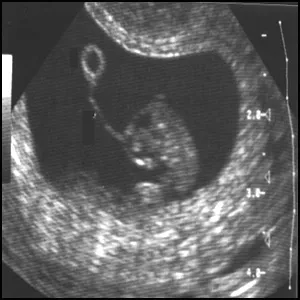

Стоит ли беременным делать УЗИ? Часть 1

Для того чтобы обращаться к врачам, нужно иметь богатырское здоровье, – гласит невесёлая народная мудрость. К массовому невежеству врачей, сегодня прибавилась возможность…